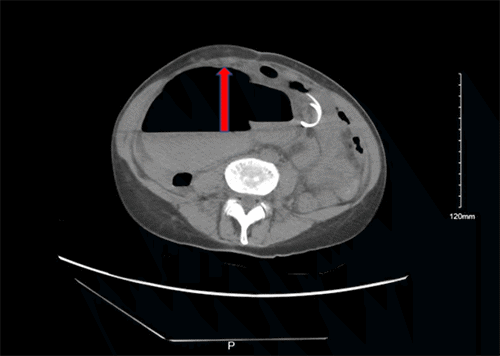

Outpatient evaluation by her gastroenterologist revealed significant dehydration and cachexia. The patient also reported right-sided abdominal pain. She denied hematochezia, melena, diarrhea, fever, or chills. Due to persistent symptoms, her gastroenterologist referred her back to the ED for further evaluation. In the ED, repeat CT abdomen/pelvis without contrast demonstrated a marked increase in cecal and proximal ascending colon distention, up to 11 cm in diameter, concerning for colonic volvulus (Figure 1). Given her relatively benign abdominal examination and multiple medical comorbidities, a decompressive colonoscopy was attempted to avoid laparotomy.

Figure 1. Preoperative Non-contrast CT Abdomen/Pelvis Demonstrating Marked Cecal and Proximal Ascending Colon Distention. Published with Permission